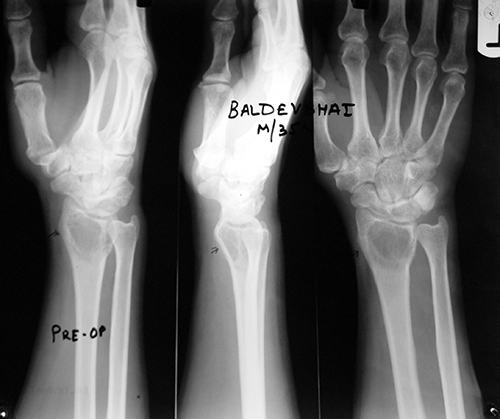

Case:2 GCT-L/E Radius

Spine Treatment In Jaipur|Best Trauma Surgeon

Pre-Op

Limb Reconstruction Doctor|Best spine surgeon

Post-Op AP

Spine Best doctor in satellite |Best Trauma Surgeon

Post-op Lateral